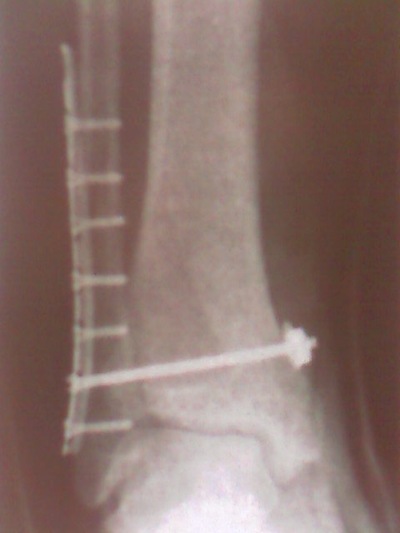

И мне недавно поставили. Точно такую же штуку как на рентгене у автора.. И нога так же левая, и даже средний болт так же торчит с другой стороны=)

Вот только на второй кости еще два шурупа. Очень хочется уже поскорее начать нормально ходить. Ну что ж, всем "киборгам" скорейшего выздоровления=)